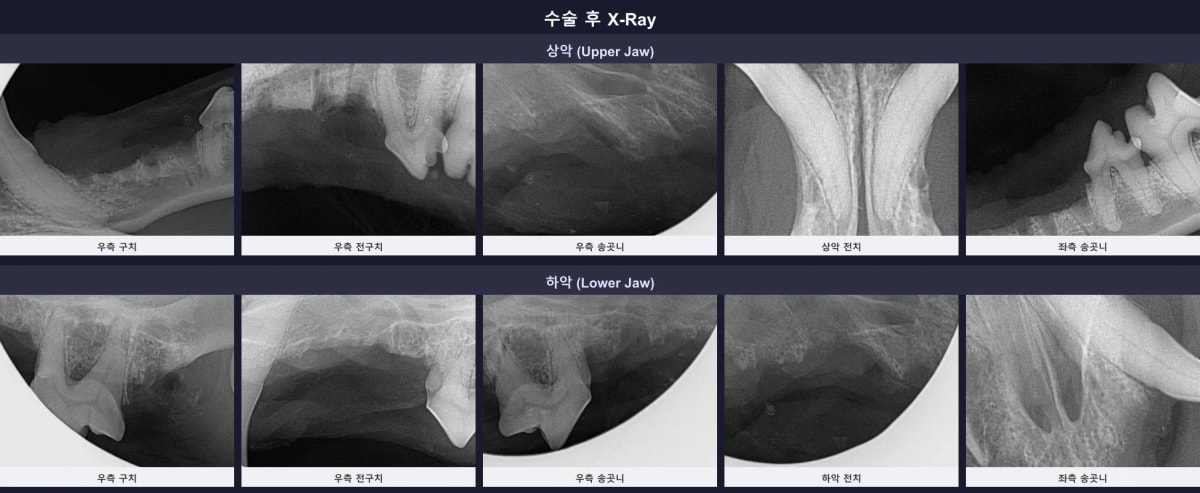

2. 수술 전 구강 엑스레이 진단

CT 검사와 더불어 구강 방사선(X-ray) 촬영을 진행한 결과, 행복이의 치주염은 매우 심각한 단계였습니다. 상하악 다수의 앞니와 작은 어금니 주변의 잇몸뼈가 심하게 녹아내려 치아 흔들림이 극심했고, 치아 406, 411번은 이미 자연 소실(Missing)된 상태였습니다.

수술 전 구강 엑스레이에서 관찰되는 중증 치주염과 치조골 흡수 소견

5. 수술 후 방사선 확인 및 기적 같은 회복

수술 직후 촬영한 구강 엑스레이에서 남은 뿌리(잔존 치근) 없이 완벽하게 발치된 것을 확인했습니다. 또한, 보존 조치를 취한 하악 송곳니(304, 404)와 어금니 부위도 깨끗하게 처치되었습니다. 회복 촉진 레이저와 불소 도포로 잔존 치아의 면역력을 높여주었습니다.

수술 후 잔존 뿌리 없이 깨끗하게 마무리된 구강 엑스레이 소견